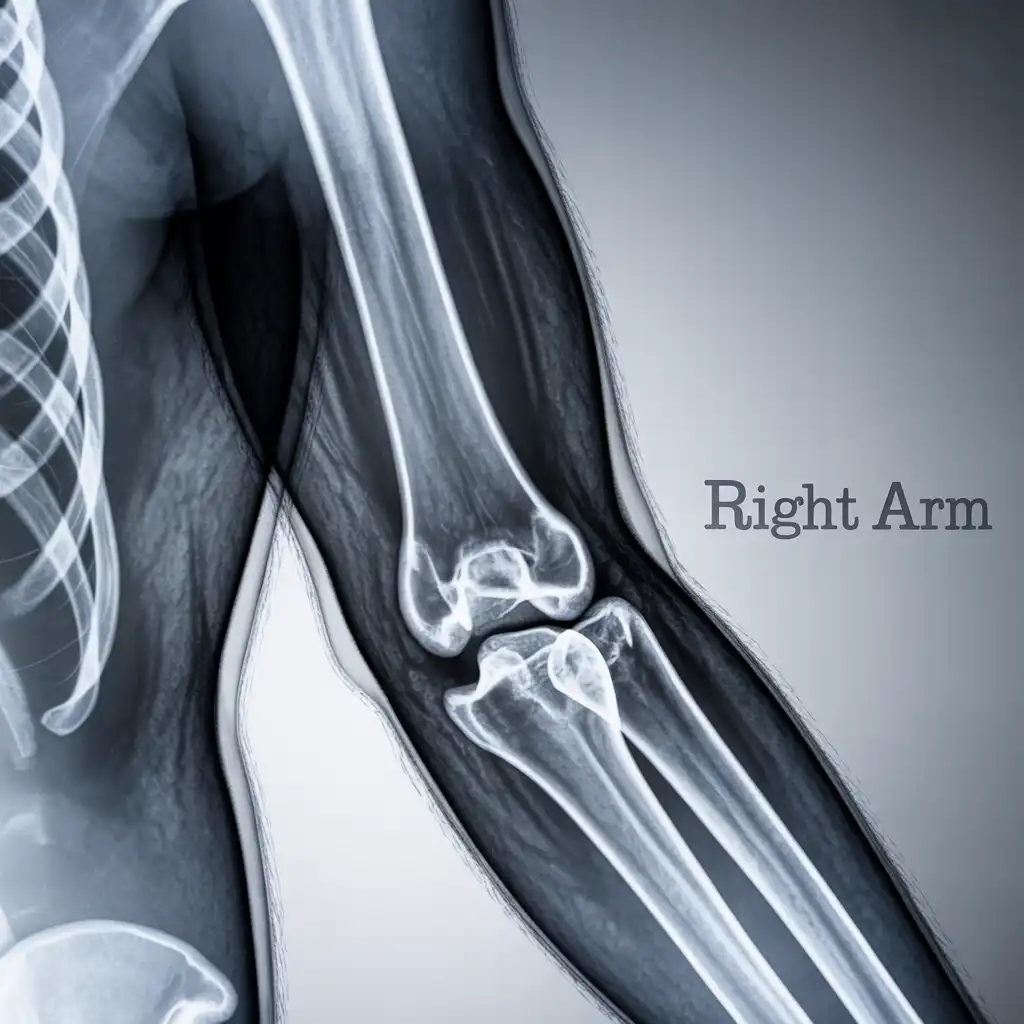

Da anni offriamo un servizio di radiografie a domicilio pensato per garantire ai nostri pazienti la stessa qualità diagnostica degli esami eseguiti in ospedale, ma con la comodità e la sicurezza della propria casa.

Abbiamo effettuato migliaia di esami direttamente presso abitazioni, residenze e strutture assistenziali, utilizzando apparecchiature digitali portatili certificate e procedure rapide e sicure.